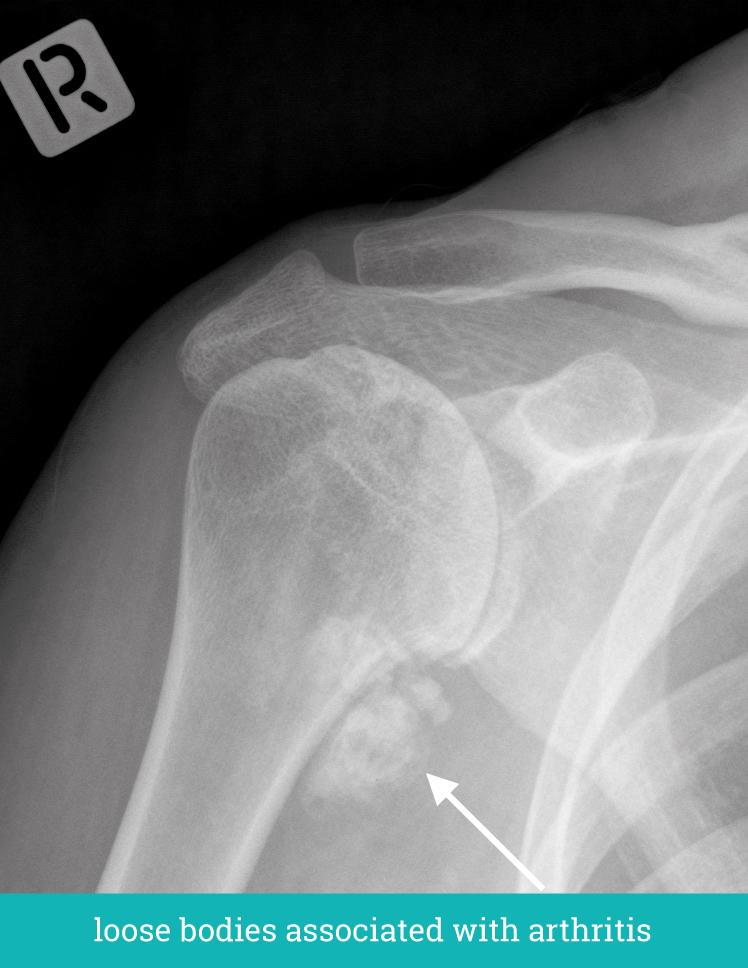

Anatomic Shoulder Replacement